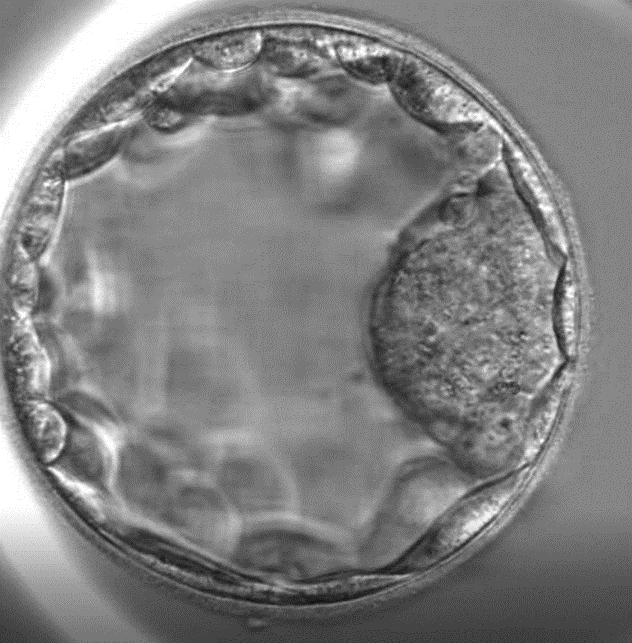

Giai đoạn phôi nang (Ngày 5 hoặc ngày 6)

Giai đoạn này phôi nang đã mở rộng, dịch nang cũng lấp đầy thể tích phôi. Các tế bào của phôi bắt đầu biến đổi phân chia thành 2 khối nội phôi bào và ngoại bì lá nuôi. Khối nội phôi bào sau đó sẽ phát triển thành bào thai, còn khối ngoại bì lá nuôi sẽ phát triển thành nhau thai.

Phoi nang ngày 5

Hình ảnh phôi nang ngày 5.

Hiện nay, phôi nang có thể là phôi ngày 5 hoặc phôi ngày 6. Nuôi phôi nang mang lại khả năng thành công cao cho quá trình thụ tinh ống nghiệm.